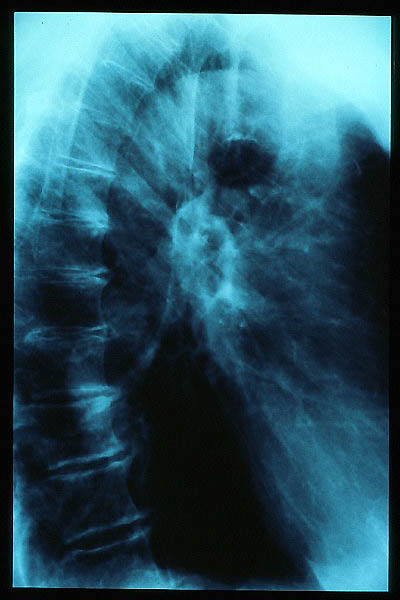

Osteoporosis. Cifosis.